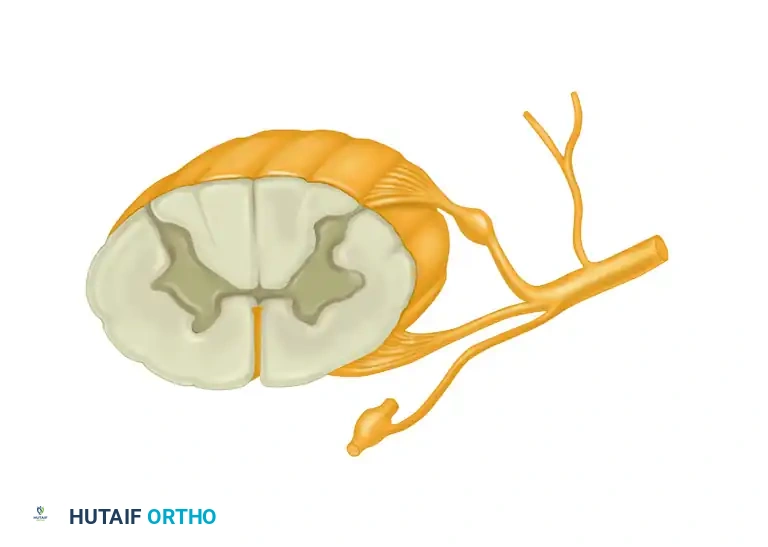

Surgical Anatomy of the Carpal Tunnel

A profound understanding of the flexor retinaculum and its surrounding neurovascular structures is paramount for safe surgical execution. The classic flexor retinaculum is a complex, tripartite structure.

The proximal limit of the retinaculum aligns with the distal aspect of the pisiform, while the distal limit extends just beyond the hook of the hamate.

Anatomically, the flexor retinaculum consists of three distinct portions:

1. Proximal Portion: Deep fascia of the forearm that courses deep to the flexor carpi ulnaris and flexor carpi radialis.

2. Middle Portion (Transverse Carpal Ligament): The thick aponeurosis spanning between the thenar and hypothenar eminences. It attaches radially to the scaphoid tubercle and the trapezium ridge, and ulnarly to the pisiform and the hook of the hamate.

3. Distal Portion: An aponeurotic extension between the thenar and hypothenar musculature.

The median nerve lies superficial to the nine flexor tendons within the canal. The recurrent motor branch of the median nerve exhibits variable anatomy (extraligamentous, subligamentous, or transligamentous) and must be meticulously protected during the distal aspect of the release.